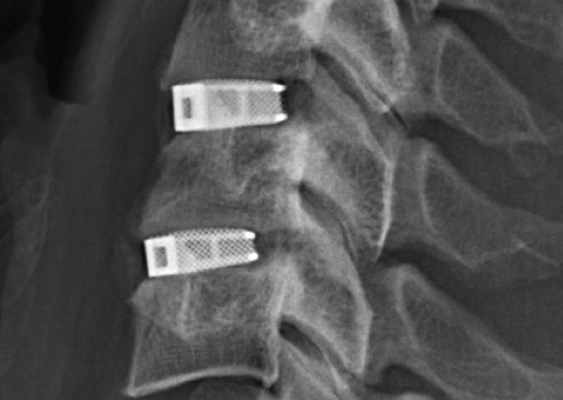

Межтеловой кейдж для фиксации позвонков

Чтобы операция дала наилучший результат, часто используется межтеловой кейдж, который должен отвечать таким требованиям:

- обеспечивать стабильность тел позвонков;

- гарантировать сохранение нормальной высоты межпозвоночных дисков, что позволяет избежать компрессии нервов;

- быть изготовленным со специальным пространством через которое, можно вводить костный цемент, искусственную костнозамещающую крошку или препаратов увеличивающих рост костной ткани ;

- Корригировать и фиксировать боковой (сагиттальный) и передний (фронтальный) баланс позвоночника;

- Удерживать нагрузку которая ложиться на ось позвоночника.

Безусловно, предельно качественное выполнение ТПФ обеспечивается при применении устройств 3-го поколения. Современные имплантируемые кейджи позволяют надежно зафиксировать патологически измененный сегмент позвоночника и устранить болевой синдром, обусловленный его остаточной подвижностью.

Кейджы межпозвоночных дисков поясничного отдела.